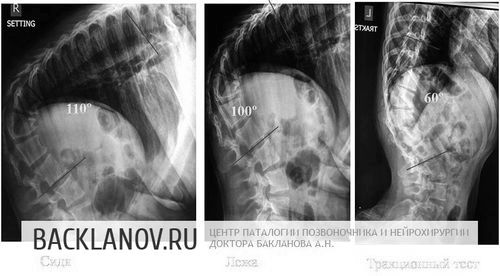

Фарафонтова Анастасії 19 років і у неї дитячий церебральний параліч, на тлі якого розвинувся важкий декомпенсований грудо-попереково-крижовий кіфолордосколіоз.

Діма талих 20 років.

У нього складне захворювання хребта на тлі дегенеративного захворювання нервової системи, що викликало формування важкого грудо-попереково-крижового сколіозу в 151˚.